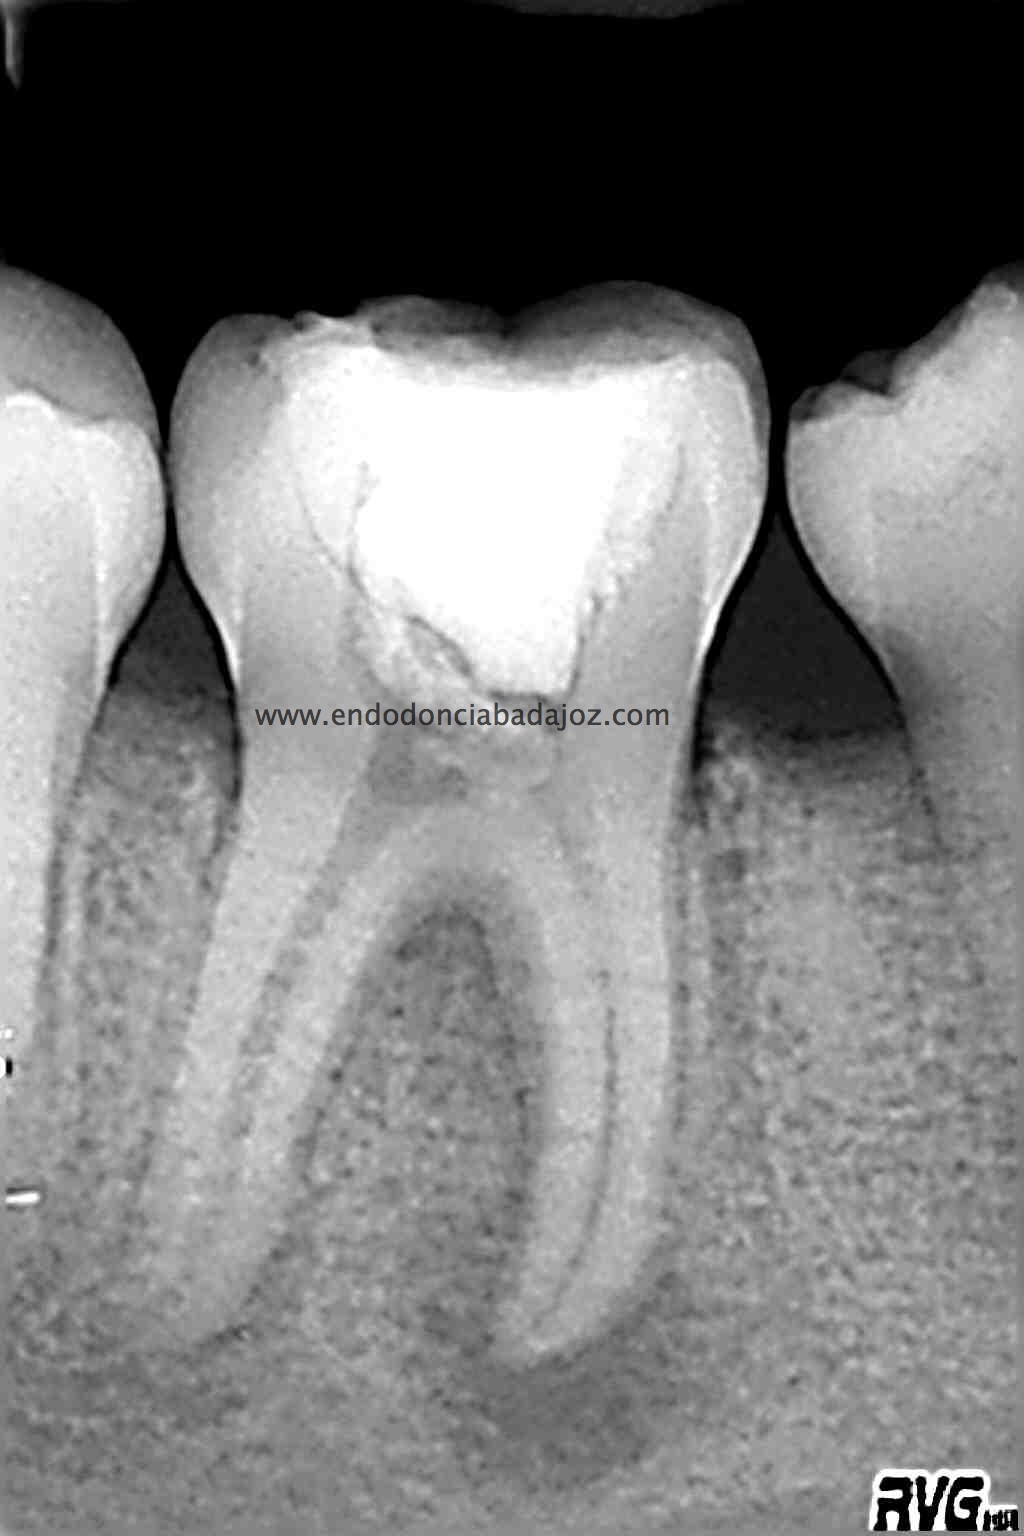

Llamamos a revisión 9 meses después a nuestro paciente:

Con estas tres proyecciones nos quedamos mucho más tranquilos y seguros de un buen sellado hermético y tridimensional des sistema de conductos de esta pieza.